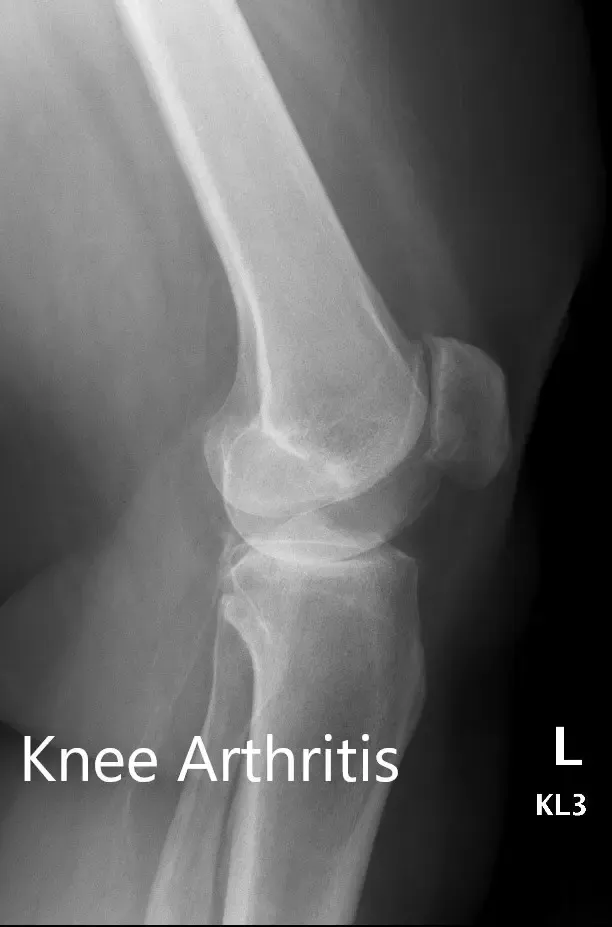

Preoperative X-ray showing the AP and lateral views of the left knee

There was no distal neurological deficit and the bilateral distal pulses were comparable. The bilateral lower extremity superficial and deep tendon reflexes were positive and comparable. Imaging revealed osteoarthritis of bilateral knees (left > right). Smoking cessation education was given to the patient.